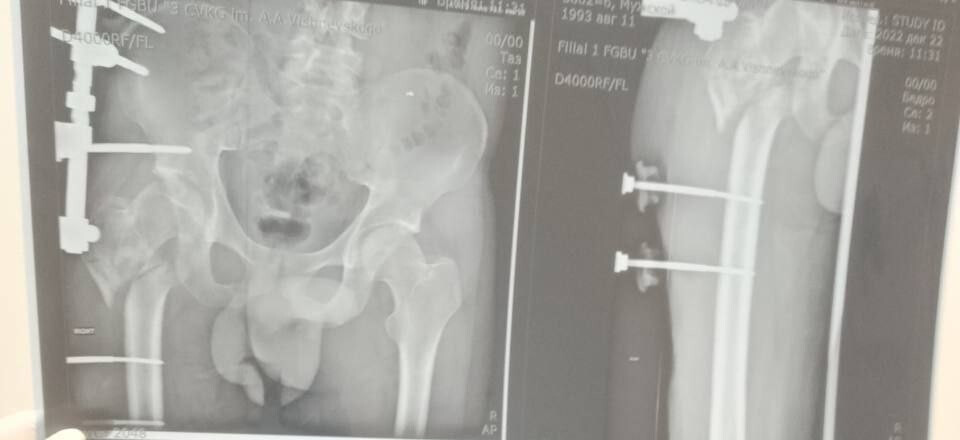

Мобилизованный 25 февраля 2022 года, военнослужащий прошел через горнило Херсонщины. 28 августа 2022 года в 23:10 под ракетным обстрелом боец получил тяжелейшее ранение правого бедра. В июле 2024 года сержант, удостоенный медали «За отвагу», был уволен со службы по состоянию здоровья.

Из-за обширных повреждений и многократных операций правая нога бойца стала короче левой на восемь-девять сантиметров. Обычное эндопротезирование изменить ситуацию не могло.

«Требовалось чудо инженерной и хирургической мысли. Чудо произошло 5 марта 2026 года в Луганске. В Луганской республиканской клинической больнице бригада травматологов-ортопедов провела операцию, которая стала финальным аккордом этой долгой истории. Вместо стандартной замены сустава пациенту выполнили сложнейшее вмешательство с использованием ревизионных систем эндопротезирования, в ЛНР такую операцию провели впервые», — проинформировала Пащенко.

Она уточнила, что главная задача хирургов заключалась не просто в установке импланта, а в восстановлении биологической оси конечности и компенсации укорочения.

Хирургам пришлось работать в рубцово-измененных тканях после десятка предыдущих операций, убрать очаги инфекции и с помощью специальных ревизионных компонентов буквально «собрать» сустав заново, вернув ноге физиологическую длину.